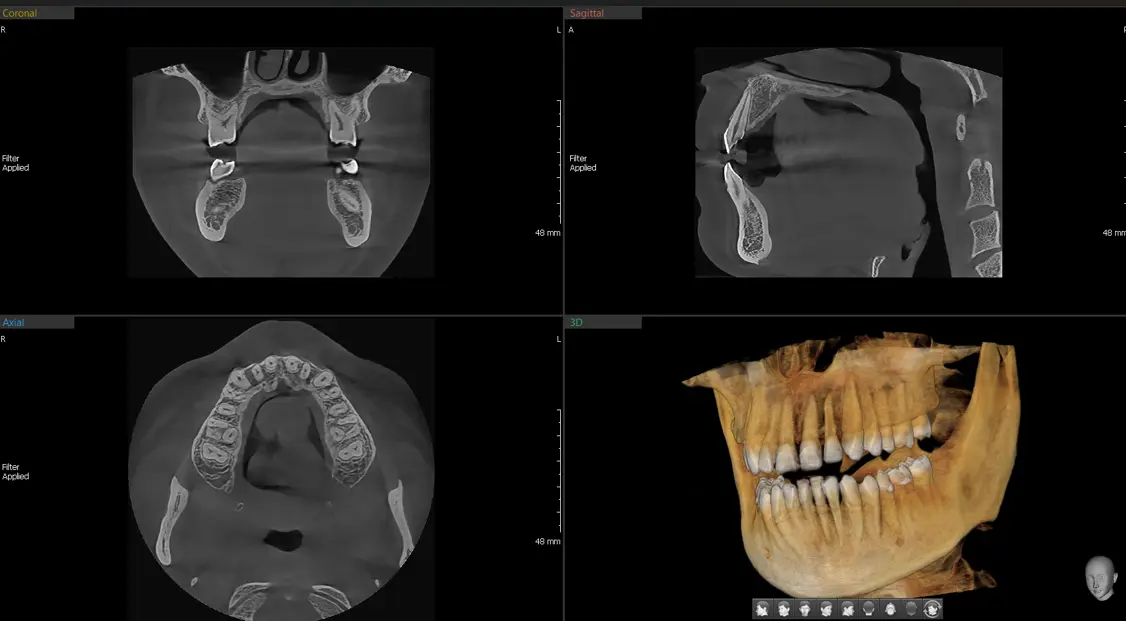

기타의료기기 관련 이미지